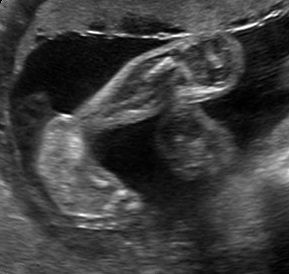

Sono-Online - fetale Fehlbildungen: "Skelettsystem"

Sonoanatomie, Biometrie, Hinweiszeichen & Diagnose von Entwicklungsstörungen, Kasuistiken, ausreichend Zeit für Diskussionen, Fallbeispiele aus der Praxis (Quiz)